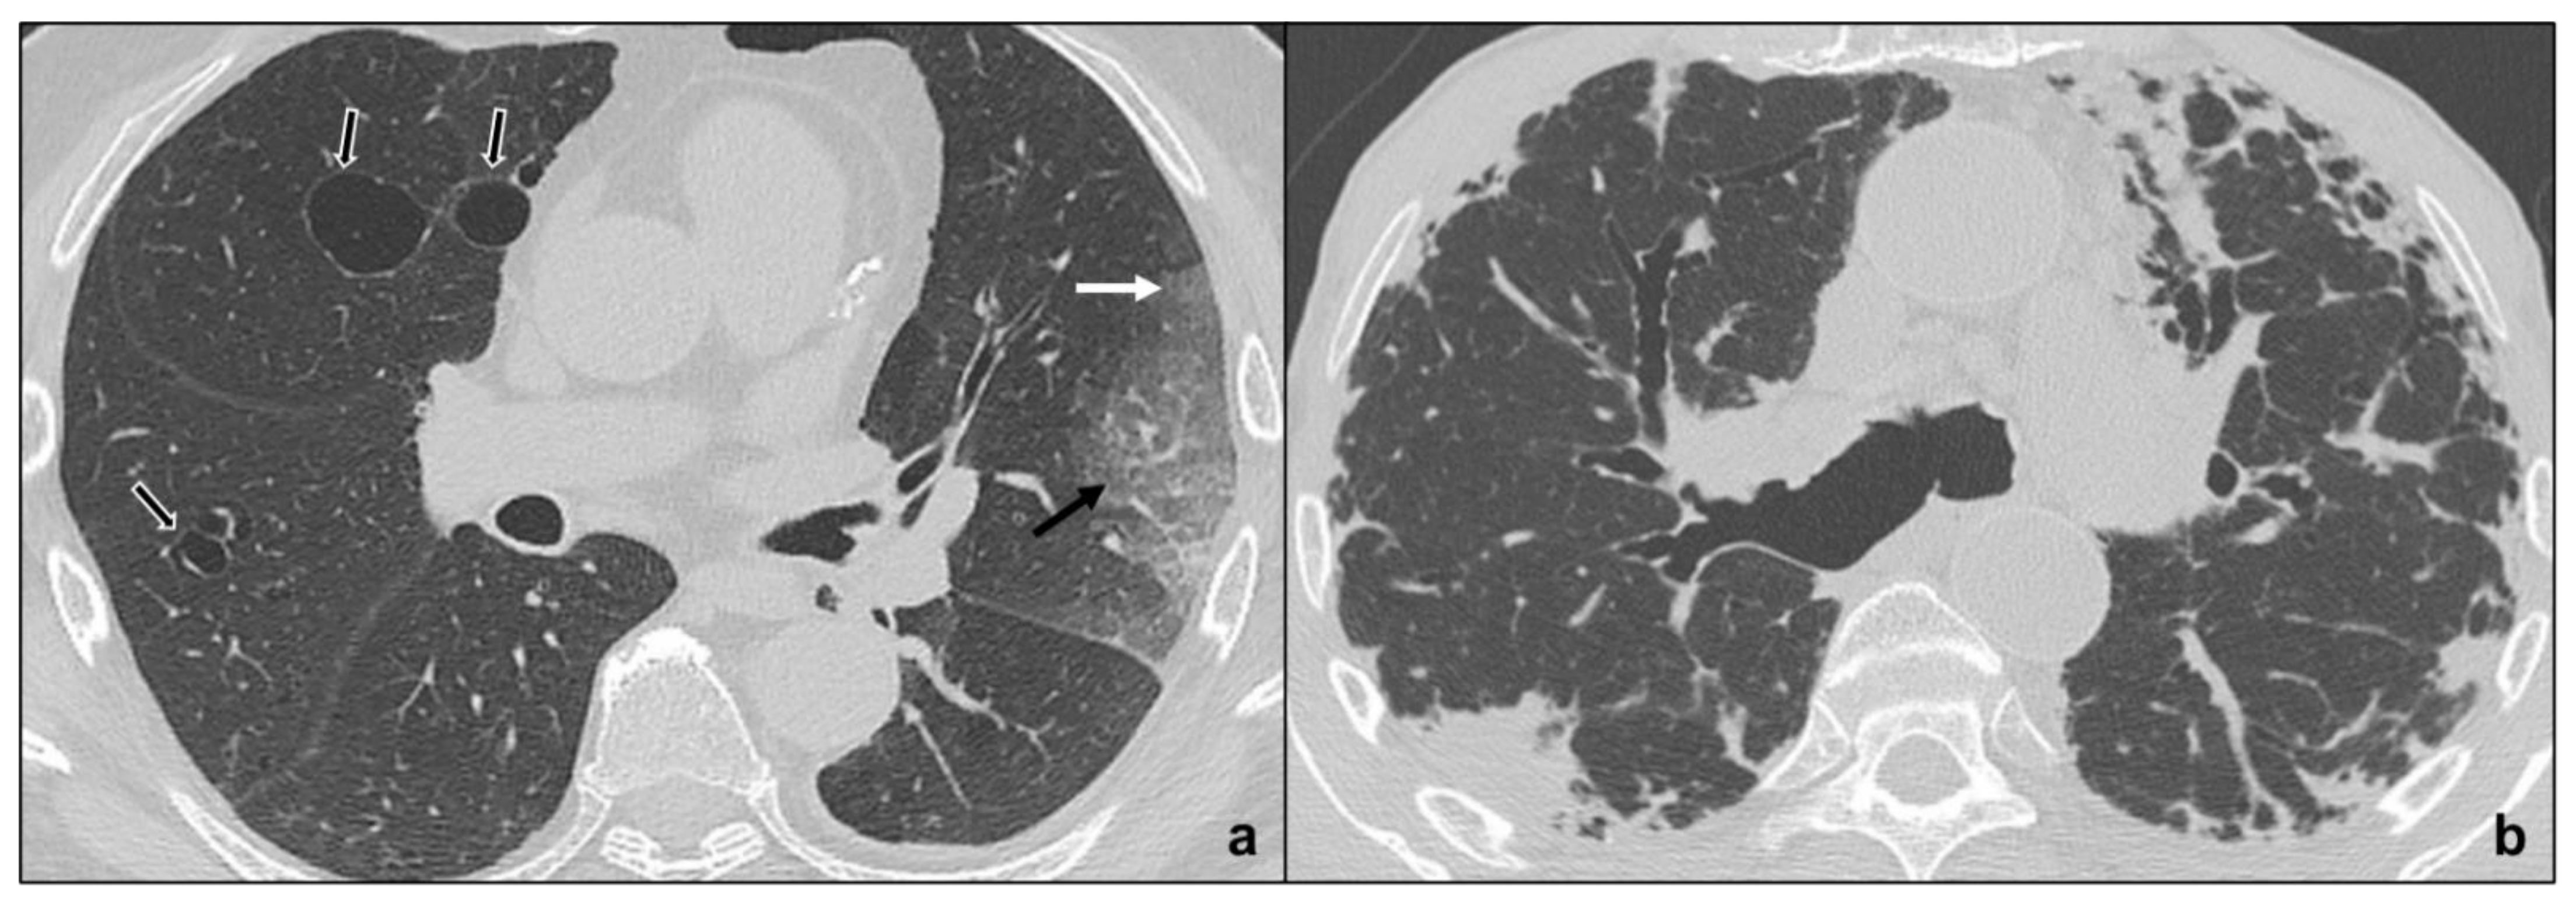

Figure 4.

Major IIPs: Smoking-Related IIPs. In (a), RB-ILD is characterized by bilateral widespread ground glass opacities, centrilobular nodules, and centrilobular (black dotted arrows), and subpleural emphysema; in (b,c), DIP shows subpleural ground-glass areas (white arrow in (b)) associated with reticular, thin opacities and centrilobular (black dotted arrows) emphysema, while in (c), perivascular cysts are evident (white-bordered black arrow in (c)).